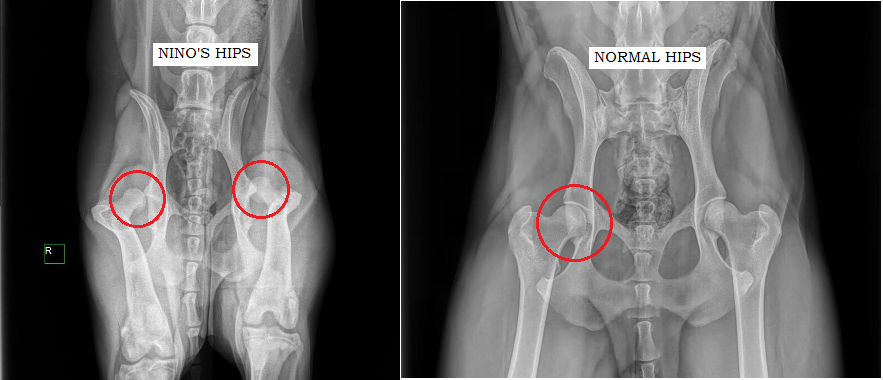

My name is Robyn McGrade. This is to handsome face of my long journey to motherhood and my biggest blessing. That cute mug belongs to my third fur babe named Nino. I adopted Nino on October 3rd, 2015. He came home with me the same day I met him. We did not share an immediate connection and it took roughly a week for me to finally catch the feels for him and that feeling has only grown stronger and stronger. I took Nino to the vet two days after I adopted him and he left the vet with a clean bill of health. I felt very confident that I made the right decision in choosing him to join my family. It became clear over time that Nino was masking some serious behavioral issues and physical ailments as well. Nino was incredibly fearful, so much so that he was once sitting on my lap outside my Starbucks store, a man approached him with a dog treat and Nino took was so shaken up by this greeting he relieved himself all over my lap. I decided to enroll him in puppy-play dates and an obedience class at a local training facility, the Canine Coach. Nino shattered every ceiling his mind had set for himself and grew into a brave, social, and loyal babe. Nino completed obedience one and obedience two, passed his Canine Good Citizenship test and hopefully can start his journey towards therapy dog work. Through this all he has found some interlopers such as mange and a nasty infection of worms not once but twice. He is a fighter in every respect of the word. I always had a feeling something was off with his hips, and our vet hoped he would grow out of the awkwardness displayed but towards the end of May we went for his check up on his worm situation and I decided to get some radiographs done on his hips. I have always assumed he had a mild form of hip dysplasia. My vet retuned with a bleak statement of “Nino’s hips are all screwed up.” My heart sank. I am programmed to expect bad but what was shared was not bad, it was the worst. Nino was basically born without hip sockets. His hip bones are for all intents and purposes free floating around his hip and he is in an incredible amount of pain.